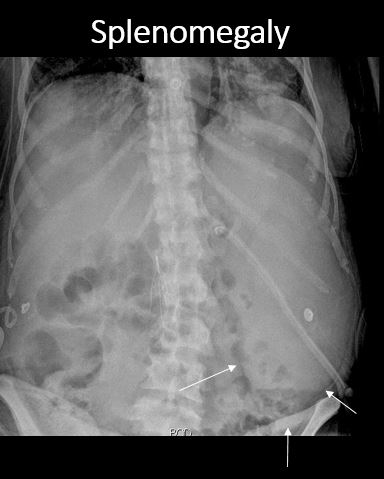

There is splenomegaly. [Yes/No]